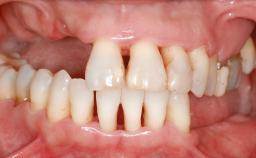

It is well known to clinicians that any removal of teeth will, over time, cause the dimensions of the alveolar ridge to be reduced by resorption of the bundle bone and by changes related to external modeling. This development is particularly evident in the crestal region with its thin buccal bone that consists of bundle bone almost entirely. The facial bone will rapidly resorb as blood supply from the periodontal ligament gets disrupted (Araújo and Lindhe 2005). There is no reason why traumatic tooth loss should not have the same consequences. It takes more than achieving implant osseointegration for a treatment outcome to be considered successful. No deficiency of bone or soft tissue is acceptable when an ideal esthetic outcome is the goal. Several articles (Sanz and coworkers 2011; Vignoletti and coworkers 2011) have reported on techniques of improving the alveolar ridge for implant treatment, notably focusing on protecting tissues from resorption.

| Soft Tissue Anatomy | Intact | Defective | |

| Bone Volume | Horizontally and vertically sufficient | Horizontally deficient | Deficient vertically or deficient vertically AND horizontally |